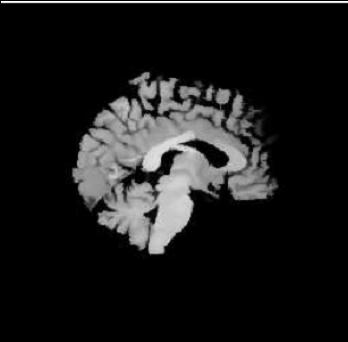

| template | coarse deformed template | fine deformed template | target | |